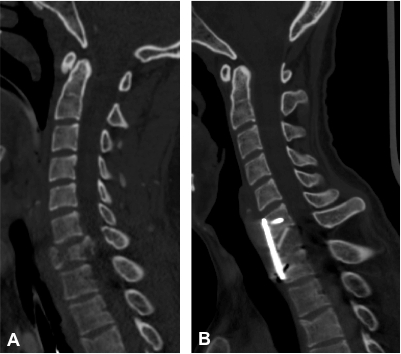

Fracture Instable Bi Isthmique De C2 Avec Hematome Epidural

An Unusual Hangman S Fracture Description And Surgical Management Sciencedirect

A New Transpedicular Lag Screw Fixation For Treatment Of Unstable Hangman S Fracture A Minimum 2 Year Follow Up Study Journal Of Orthopaedic Surgery And Research Full Text

Surgical Management Of Axis Traumatic Spondylolisthesis Hangman S Frature